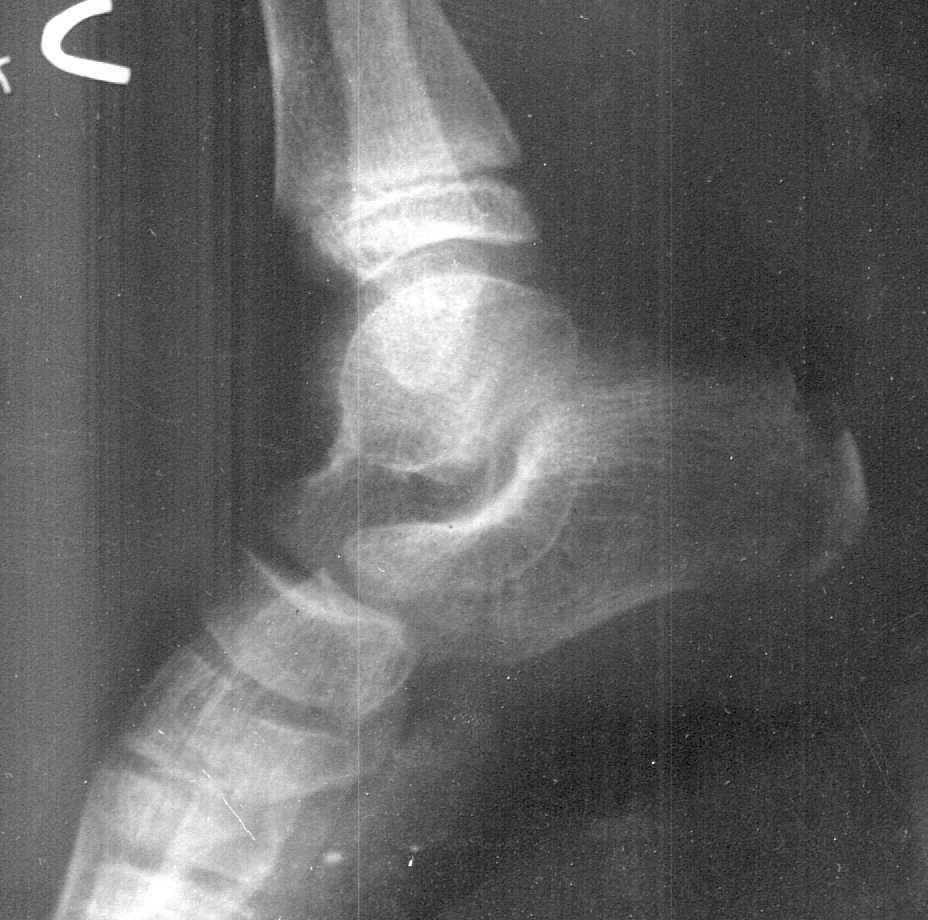

The case shown in figure 3 was a male, who was brought to the author for alleged sodomy on him. The police wanted to know his age, as a tender age could lead to stricter punishment to the accused. If we look at the X-ray carefully, we see that the head of femur has appeared. This meant that the age was above 1 year. But the greater trochanter has not yet appeared which allowed us to say that he was below 4 years. The actual age of the boy was found to be 2 and a half years from other evidences.

The case shown in figure 4 is also a male. He was brought as he had stolen some jewelry from a female, and he had applied for confinement in a Children's home. In this case, the tri-radiate cartilage can easily be seen which allowed us to say that the person was above 13 years and below 15 years of age. However a very faint shadow of lesser trochanter could also be seen. Lesser trochanter appears at around the age of 14 years. Opinion given was that the child was between 14-15 years.